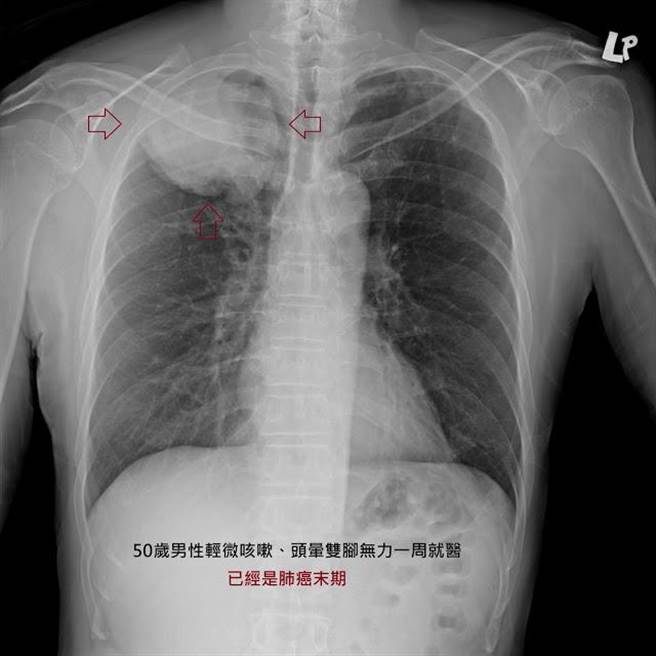

50多岁的男性患者、偶尔咳嗽一个多月,最近感到头晕双脚无力,就医全身健检后发现已经是肺癌末期。(图撷自苏一峰医师部落格)

苏一峰在部落格撰文提到,自身接触的2个病例,一是50多岁的男性患者、偶尔咳嗽一个多月,最近感到头晕双脚无力,就医全身健检后发现已经是肺癌末期,肺部已经有10公分大的肿瘤且合併脑部多转转移,如果不接受任何治疗,任癌症发展下去剩余寿命可能只有3个月。另一位是70多岁男性,轻微咳嗽、肩膀酸痛就医,经X光检查意外发现,肺部肿瘤已经6-7公分大,造成局部神经压迫导致肩膀疼痛!

苏一峰说,一般来说肺癌要大于一公分以上,才有机会被胸部X光发现,而更困难的是胸部X光有许多死角无法看清楚,譬如:心臟纵膈的前后,肺门大血管处,还有肺尖处或横膈下方、最后还有骨头交接处等等,这些死角都会妨碍肺癌的发现。许多躲在死角的肺癌都长到四、五公分了,X光仍然不容易被发现!而肺癌大于一公分以上,就有转移的可能性,也因为如此不少肺癌患者明明去年才照过胸部X光,今年却被诊断发现是末期肺癌。